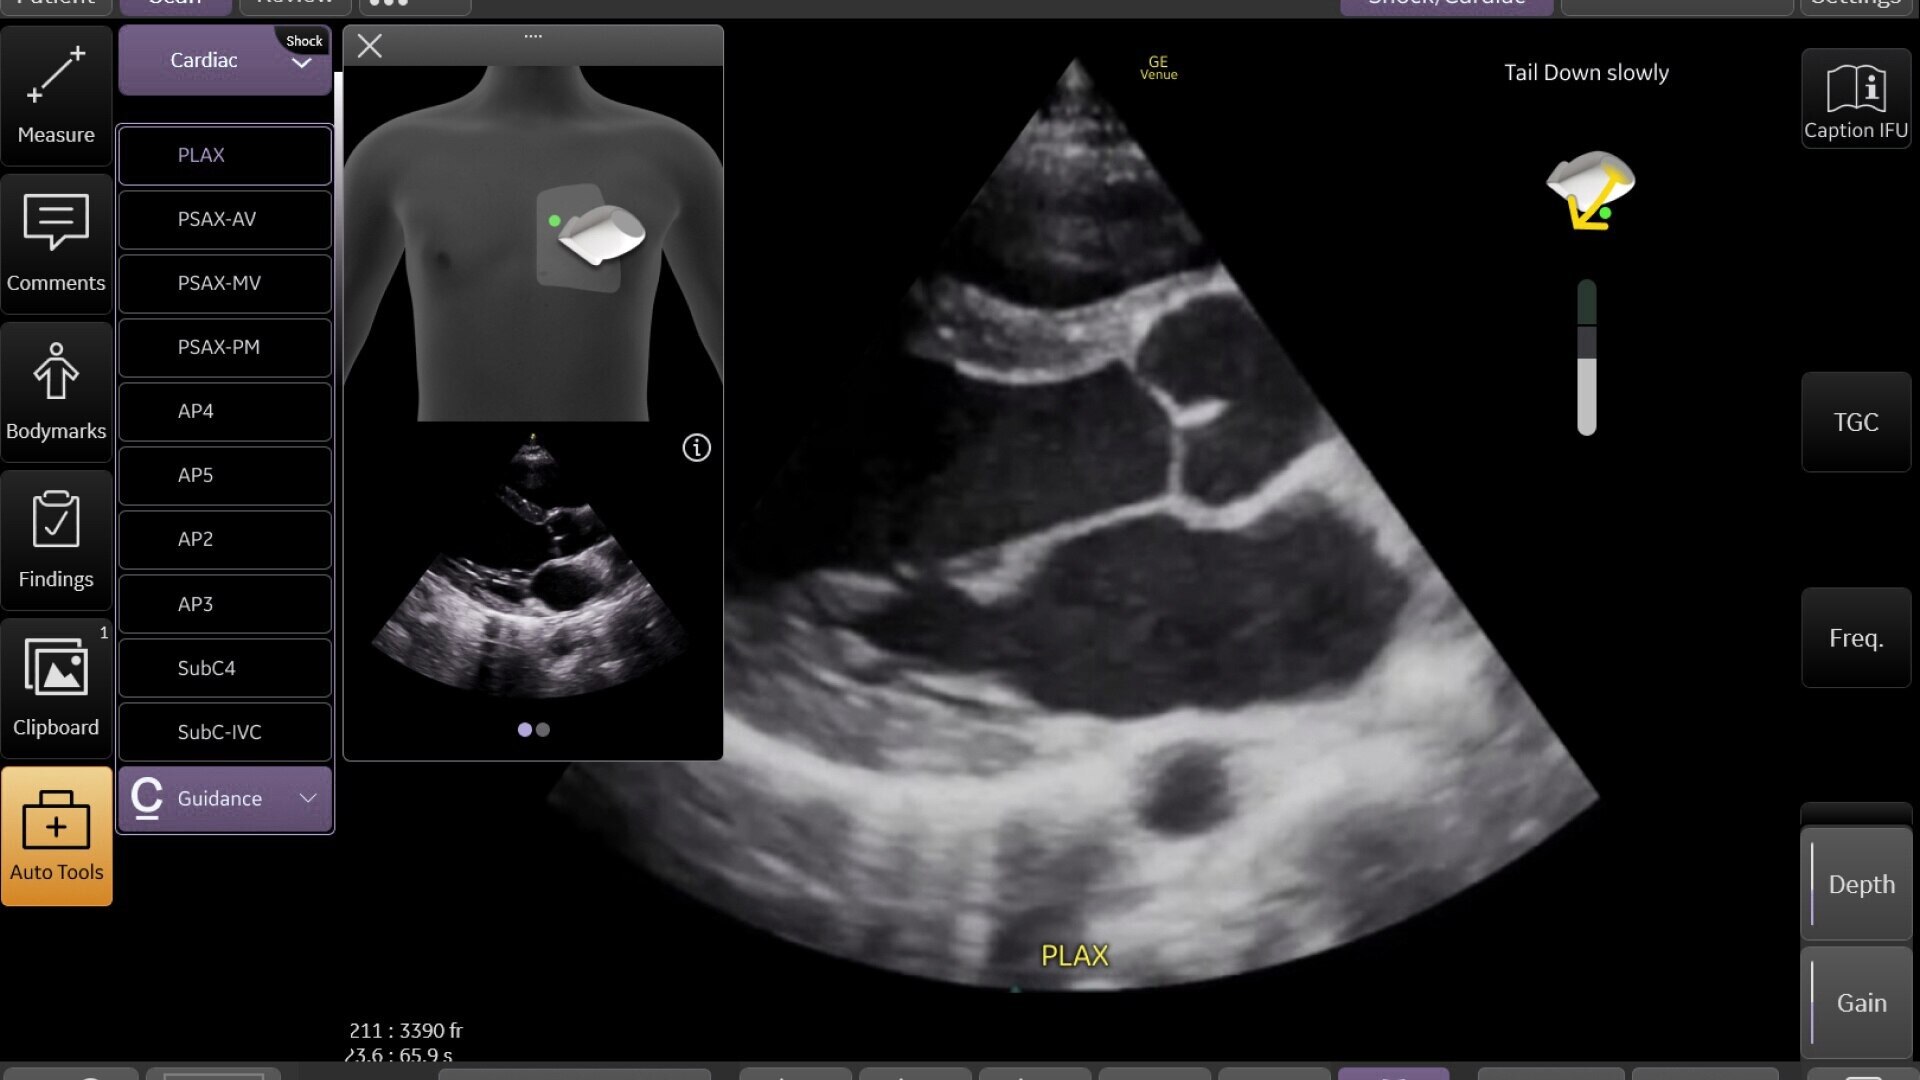

Automated tools

Simplify your workflow with AI-enabled clinical tools.

Helping drive consistency from user to user (whether one is an ultrasound novice or expert), Venue Fit features AI-enabled resources that help clinicians work smarter and more efficiently. Utilizing proprietary algorithms, we synthesize data from numerous patients to ensure accurate calculations for clinical confidence.